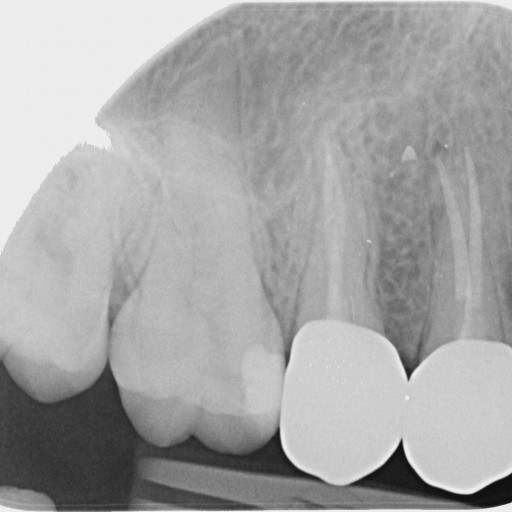

Implantace

Zavádíme implantáty Straumann, Inno, Dio, Megagen. Provádíme potřebné augmentace kosti, sinus lift. Další protetické ošetření může provest ošetřující lékař.